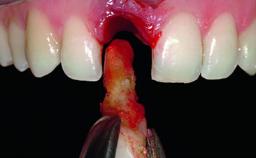

A 36-year-old male patient with a compromised maxillary central incisor was referred by his general dentist for consultation. The patient’s chief complaints were the gradual debonding of a temporary crown on the right central incisor and unsatisfactory esthetics due to an increasing diastema between the right central and lateral incisors. The patient reported a traumatic event some years previously, when a crown had been placed after root-canal treatment. The referring dentist wanted to provide a new crown restoration, but was concerned about the condition of the residual root. Anamnesis was negative for any other dental or periodontal pathology in the remaining dentition. The patient reported taking no medications: He was a smoker (10 to 15 cigs/day) and had realistic esthetic expectations.

Bone Augmentation Horizontal|Simultaneous|Staged

Soft Tissue Grafting Simultaneous

Bone Volume Deficient horizontally, requiring prior grafting